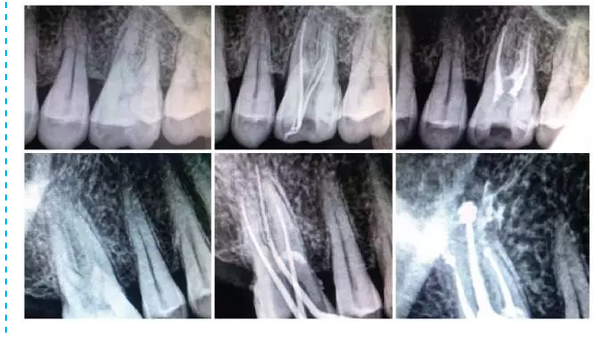

在臨床中選擇使用MM1500音波手機的基本步驟:選擇病例,急、慢性牙髓炎,根尖周炎,根管無鈣化,或鈣化根管已疏通,根管無明顯彎曲者。常規(guī)開髓,拔髓。使用手用器械大錐度鎳鈦銼去除根管口牙本質(zhì)領,使用10號或15號銼針用根管長度測量儀測長,并插入擴大針X線根尖片定位。按操作要求,將MM1500音波手機與牙科綜合治療臺上渦輪機工作端相連接,附帶的內(nèi)置式?jīng)_洗裝置使用蒸餾水,氣動壓力為30kPa,功率設置根據(jù)Rispisonic銼針磨損程度,從低檔至中檔選擇,設置工作長度,預彎銼針。以15號銼針開始預備,始終保持銼針在根管內(nèi)有一定的松動空間,與根管壁輕度接觸,并沿根管長軸提拉,幅度1~2 mm,待銼針可以在根管中較自由進出時,以大一號的手用器械K型銼行標準法修形后換同號的Rispisonic銼針,同法預備至所要求的號數(shù)。每更換一次器械均用新鮮配制2.5 g/L次氯酸鈉溶液沖洗根管,并要求每個根管至少預備到比初始號大兩個號以上。預備過程中用170g/LEDTA 液和125g/L 次氯酸鈉液交替沖洗根管。預備后,兩組均用氫氧化鈣糊劑行根管封藥消毒,一周后復診, 符合根充條件,即行根管充填。試尖合適,采用標準牙膠尖和AH-Plus 根管封閉劑側向加壓充填法充填根管。根管充填后行常規(guī)X線檢查。改換修復科進行修復治療。

總之,MM1500音波手機的蕩洗和根管預備功能并重。MM1500音波手機已經(jīng)改變了超聲根管器械在根管治療中只能起輔助作用的情況。MM1500音波手機的使用可減少、減輕疼痛反應,但應注意配合使用手用器械,避免發(fā)生臺階形成、根管側穿。聲波與手用器械聯(lián)合使用,其雖不能提高根充填質(zhì)量,但能減少EIE的發(fā)生,減少治療感染根管的療程次數(shù),尤其是良好的預備能力,與沖洗同時進行,優(yōu)化了傳統(tǒng)以針筒沖洗根管的步驟,使包含了清理和成形這兩方面的根管預備,得以簡便迅速,提高了工作效率。